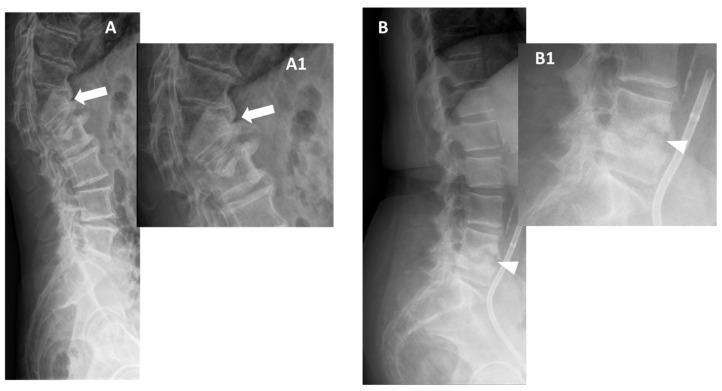

Spondylodiscitis is defined by infectious conditions involving the vertebral column. The incidence of the disease has constantly increased over the last decades. Imaging plays a key role in each phase of the disease. Indeed, radiological tools are fundamental in (i) the initial diagnostic recognition of spondylodiscitis, (ii) the differentiation against inflammatory, degenerative, or calcific etiologies, (iii) the disease staging, as well as (iv) to provide clues to orient towards the microorganisms involved. This latter aim can be achieved with a mini-invasive procedure (e.g., CT-guided biopsy) or can be non-invasively supposed by the analysis of the CT, positron emission tomography (PET) CT, or MRI features displayed. Hence, this comprehensive review aims to summarize all the multimodality imaging features of spondylodiscitis. This, with the goal of serving as a reference for Physicians (infectious disease specialists, spine surgeons, radiologists) involved in the care of these patients. Nonetheless, this review article may offer starting points for future research articles.

脊椎椎间盘炎是由涉及脊柱的感染性疾病所定义的。在过去几十年中,该疾病的发病率持续上升。影像学在疾病的各个阶段都起着关键作用。实际上,放射学工具在以下方面至关重要:(i)脊椎椎间盘炎的初始诊断识别;(ii)与炎症性、退行性或钙化性病因进行鉴别;(iii)疾病分期;以及(iv)为确定所涉及的微生物提供线索。后一个目标可以通过微创程序(例如CT引导下活检)实现,或者通过分析所显示的CT、正电子发射断层扫描(PET)CT或MRI特征进行非侵入性推测。因此,本综述旨在总结脊椎椎间盘炎的所有多模态影像学特征。目的是为参与这些患者护理的医生(传染病专家、脊柱外科医生、放射科医生)提供参考。尽管如此,这篇综述文章可能为未来的研究文章提供起点。